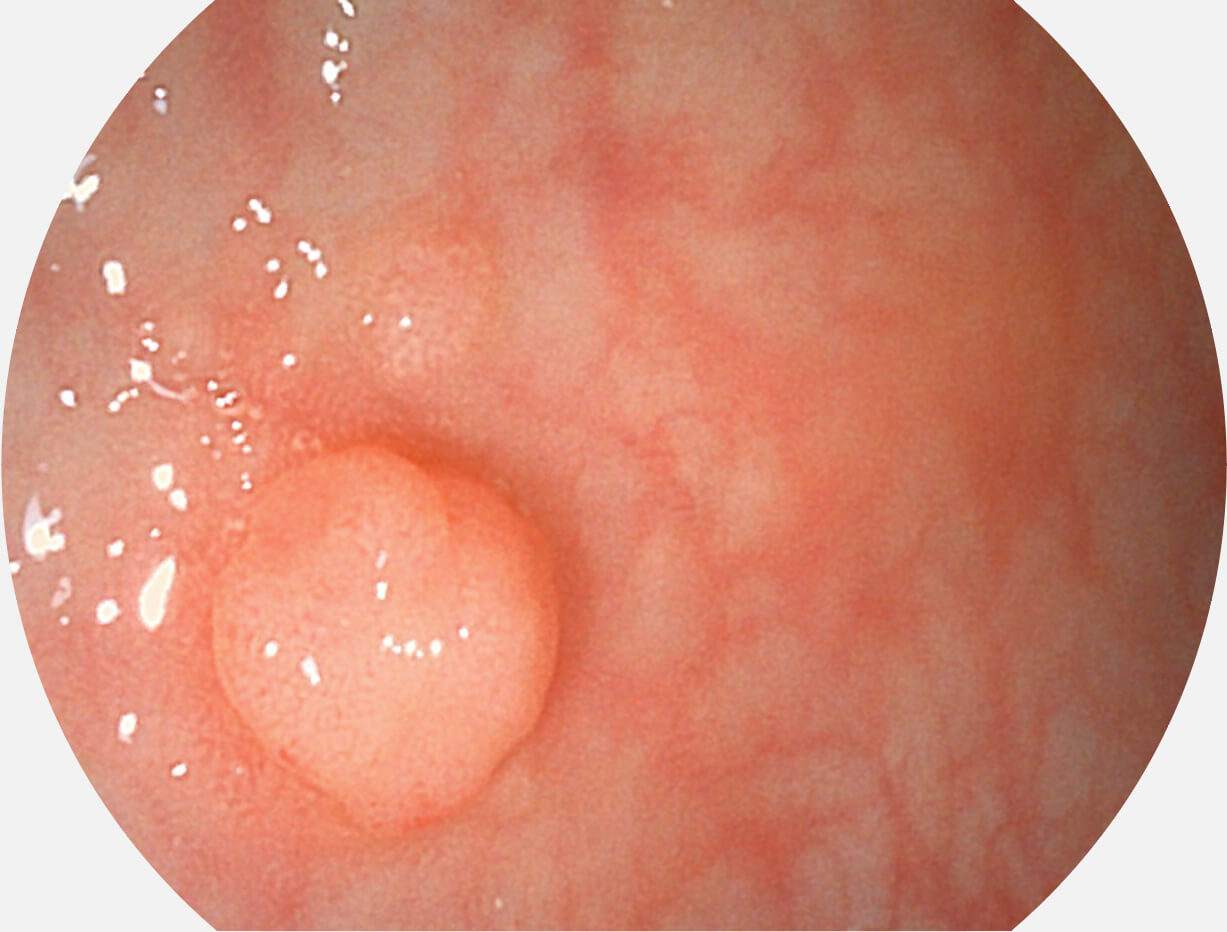

强调浅层黏膜结构的同时,保证照明亮度和提升浅层微血管与中层血管颜色对比度,病变边界更清晰。

白光图像

VIST图像